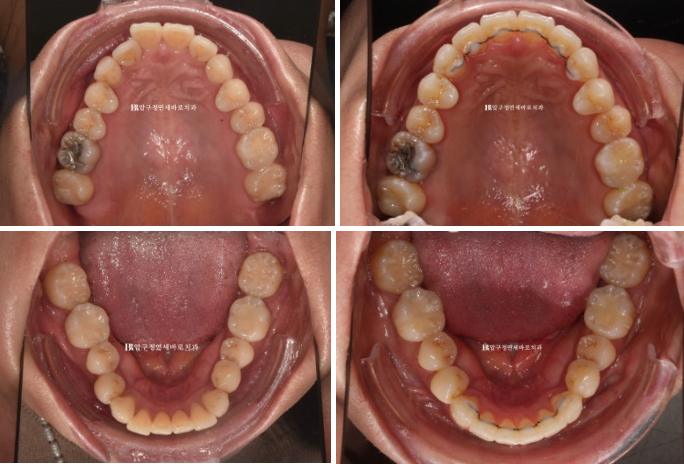

23.10

The blue arrow shows the front teeth biting in the wrong direction.

Because the teeth that bite in the wrong direction are positioned backward, the two central incisors appear relatively protruded.

The molar occlusion is in fairly good condition.

24.01

Left - Before treatment / Right - After treatment

23.10~24.01